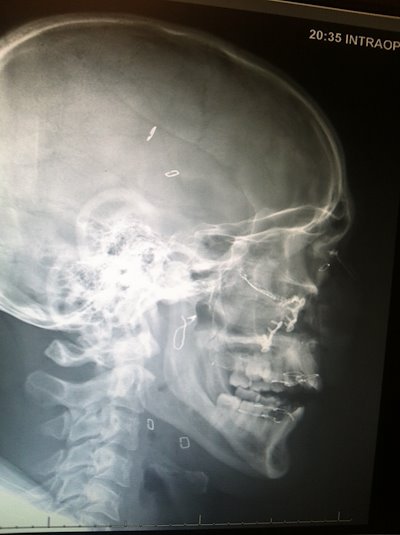

I had a small hiccup in July 2014. During a horrific crash nearing the finish of the Manhattan Beach Grand Prix Pro road cycling race, I was bumped into a crowd control gate (occupational hazard) and shattered nearly every bone in my mid-face. My bicep bone came through the skin in an open fracture and I was in a coma for a little under a week. I had the most excellent team of surgeons in Dr. Jerome Wilson, Dr. Ted Chen, and Dr. Newt Eichorn. They were able to piece me back together with a 3D model recreating my facial bones using titanium plates, screws, and even harvesting a rib to fashion a nose out of it. The joke is that I had my mother’s nose before and now I have a “RibNose” that more resembles my dad’s shnoz. I had my jaw wired shut for a month, and a tracheotomy hole cut into my neck to ensure a safe airway during surgery.